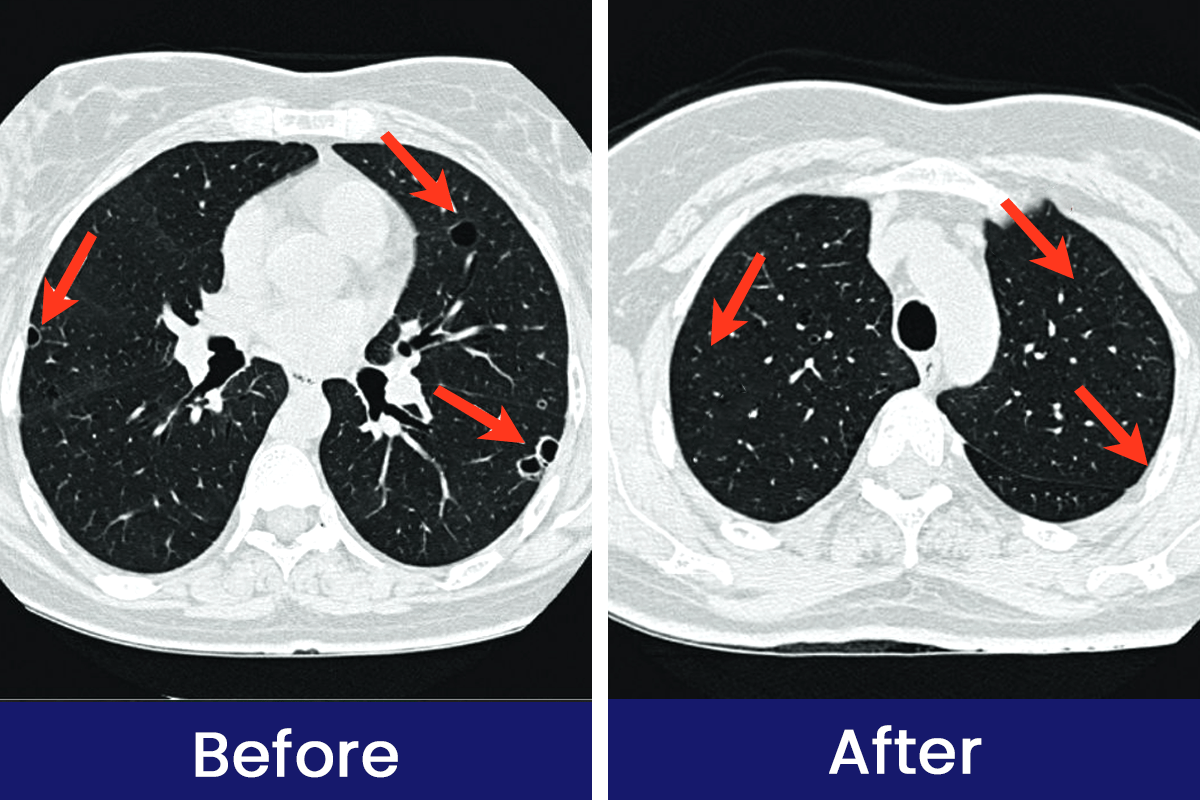

See How Luhaka™ Nicofree is Helping Customers Breathe Easier and Live Smoke-Free Every Day!